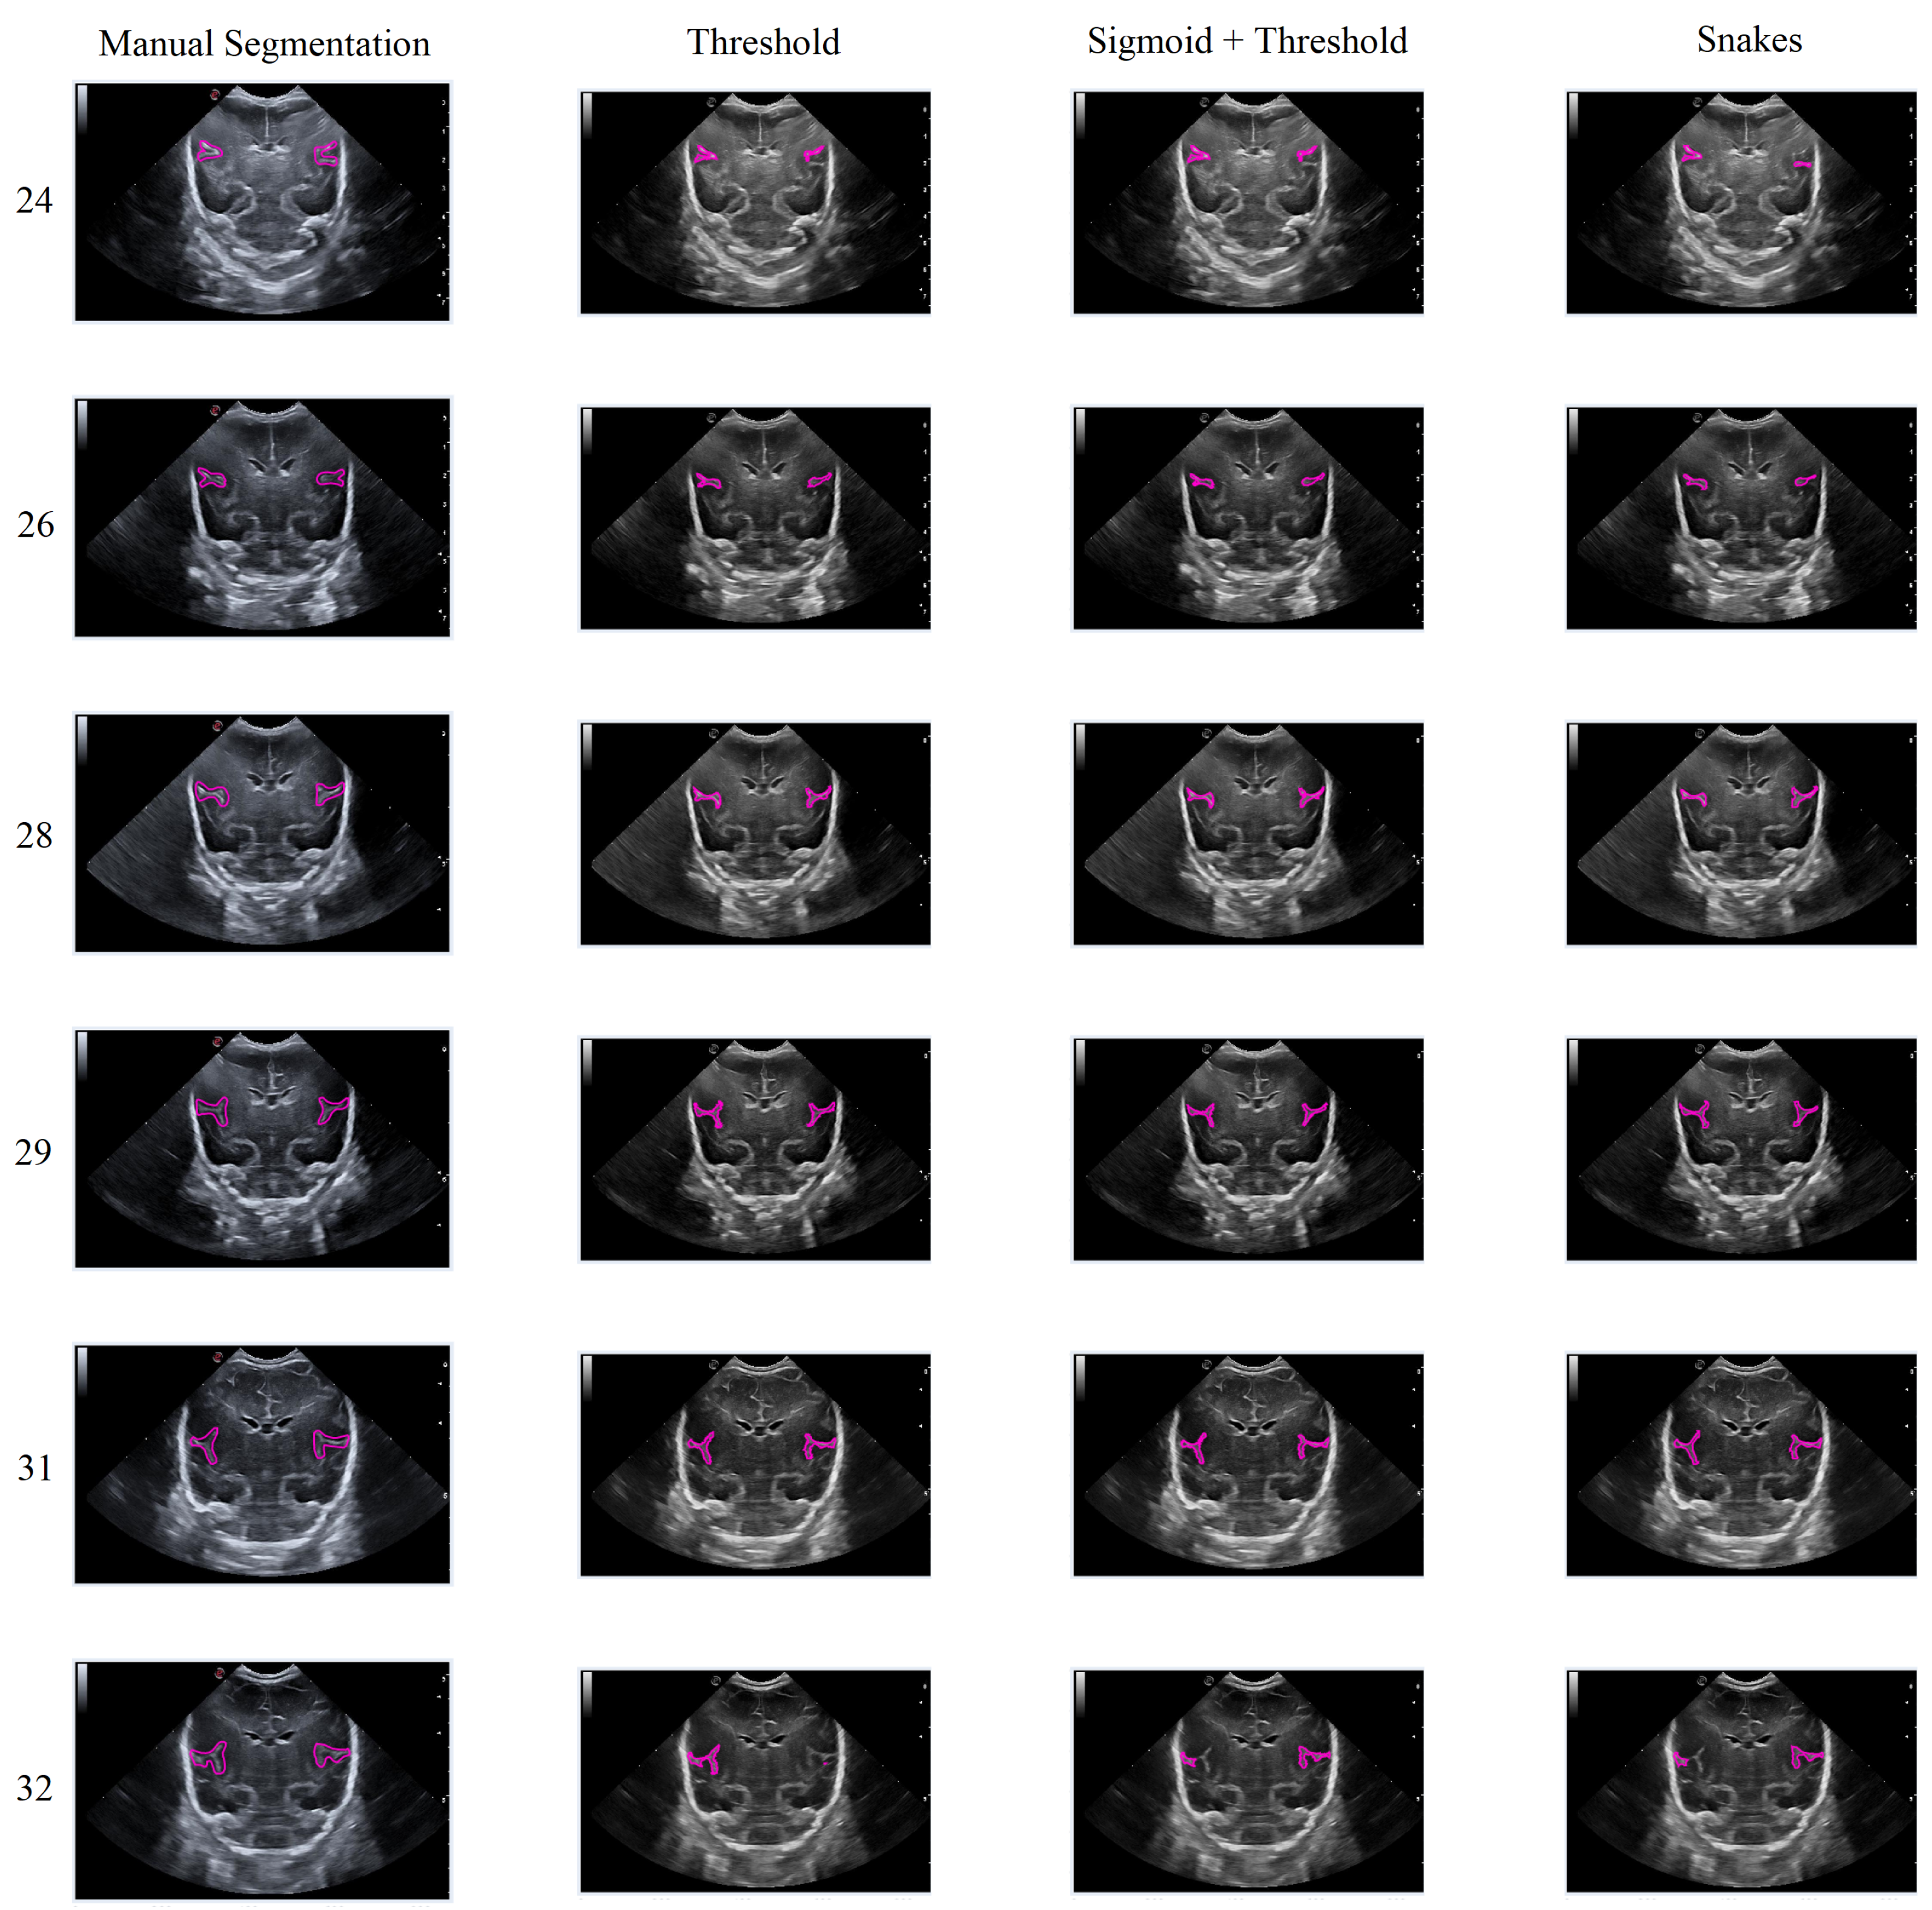

In general, the results obtained from the semiautomatic process have been mostly accurate with good precision, except in cases where the noise was too high, making it difficult to identify and define the groove. Nevertheless, the defined algorithm largely fulfills its objective, allowing for modifications to be made to the segmentation results without having to execute the algorithm again. An example of this can be seen in Figure 15, which displays different samples of segmentation on the Sylvian furrow and how it evolves throughout several weeks of gestation in a baby. The figure shows the manual slicer, Threshold, Sigmoid + Threshold, and Snakes algorithms in the columns from left to right. Each row represents the week of gestation when the ultrasound was taken (from top to bottom: 24, 26, 28, 29, 31, and 32).

In general, the algorithms provide good results in cases where the groove is moderately defined, and noise does not affect the structure significantly. However, in areas with high levels of noise, the algorithms tend to struggle to define the groove, resulting in an irregular contour that may not accurately represent the original structure.

Figure 15. Segmentation examples for the Sylvian sulcus (Manual segmentation), carried out between weeks 24 and 32 of gestation of a mime baby applying the different segmentation methods (Threshold, Sigmoid + Threshold, and Snakes).